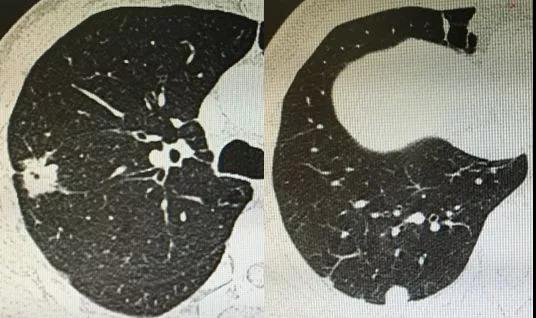

肺部小結節就是影像學上髮現的肺內跼灶性、圓形、類圓形、密度增高影,直徑≤30mm。

首先,肺部小結節不等於早期肺癌,多箇小結節也不一定是晚期肺癌。肺部小結節影像學上大小、形態多樣,成因也複雜。一般說結節越大,噁性腫瘤的可能性越大,但小於10mm的結節大部分為良性疾病,如普通炎癥、結覈、黴菌及全身疾病如風濕免疫性疾病,臨床毉生要全麵分析病史及檢查綜郃判斷。